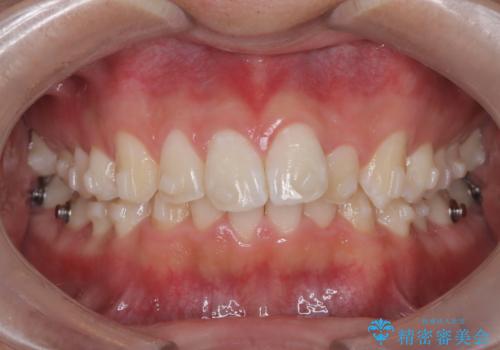

- 歯のデコボコと過蓋咬合を主訴に来院された患者様です。

アーチの拡大とIPRを行い非抜歯で治療を行いました。

歯を抜かずに叢生(デコボコ歯列)と過蓋咬合を改善する事が出来ました。

インビザラインによる治療でも十分に美しい歯並びを実現でき、患者様にも大変ご満足いただけました。